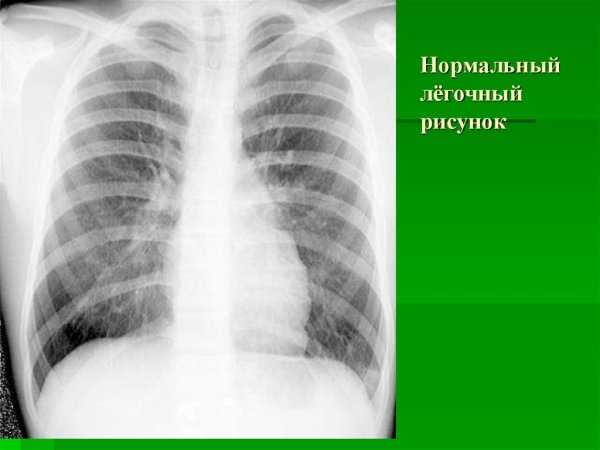

Легочный рисунок в норме

Нормальный легочный рисунок на рентгенограмме